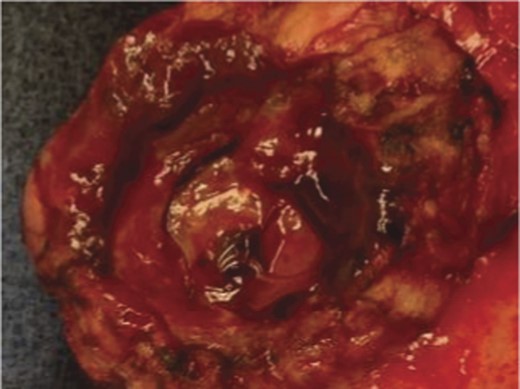

A frail 77-year-old multiparous Caucasian female with a history of aspirin and naproxen use, presented to an outside hospital with epigastric pain and an episode of hematemesis. She had no prior history of peptic ulcer disease, alcoholism or pancreatitis. The patient was hemodynamically stable with an acute anemia (hemoglobin of 7.7 g/dl), which prompted transfusion of 2 units of PRBC and transfer to a tertiary care facility. Upon transfer, she underwent an emergent upper endoscopy, which revealed a large amount of blood with clots in the lumen of the stomach. However, sufficient suctioning of the large intra-gastric clots was not possible; hence, an underlying etiology was not obtainable. The patient subsequently underwent a diagnostic angiography, which revealed a 4 cm mid-SA pseudoaneurysm with active contrast extravasation into the stomach which can be seen in Figs 1 and 2. The radiologist decided to perform a transcatheter arterial coil embolization of the artery to halt the active bleeding. A post procedure angiography revealed no further contrast extravasation. A planned upper endoscopy was repeated the following day that revealed some residual clotted blood in the stomach, no active bleeding and a deep 4 cm gastric ulcer. Due to the high risk of re-bleeding, the patient was optimized physiologically and consented and prepared for exploration. Intraoperatively we observed that the SA pseudoaneurysm was densely adherent to the posterior wall of the stomach, and coursing through an inflamed distal pancreas. We decided to proceed with an en bloc resection of SA pseudoaneurysm, distal pancreatectomy, partial gastrectomy and splenectomy. After the celiac axis was surgically defined, proximal and distal SA controls were obtained and a circumferential posterior gastrotomy was made. There was a visible posterior gastric mucosa to splenic arterial fistula, with the radiologically inserted embolic coils clearly visible. This can be seen in surgical specimen (Figs 3 and 4). Once the stomach was reflected, the splenic vessels and the pancreas were divided and the specimen removed. The pathology reports indicated active gastritis with transmural ulceration into the splenic artery (SA) and adjacent pancreatic tissue. No malignant cells were identified in the gastric or pancreatic tissue and the SA was not aneurysmal (Fig. 5). During the postoperative period, the patient had an uncomplicated recovery and was discharged on day 5.

Surgical specimen of en bloc partial gastrectomy, distal pancreatectomy and splenectomy.

Surgical specimen of en bloc partial gastrectomy, distal pancreatectomy and splenectomy. Embolic coils visible in arterial lumen.

It appears that the true SA aneurysm causes pressure on surrounding viscera as it increases in size. During this time a fistulus connection is formed, and once it ruptures, it can present as GI bleeding. Hence, the aneurysm is the causative element. However, in the case of an SA pseudoaneurysm, a pathology of the surrounding viscera leads to vessel wall contact with digestive gastric or pancreatic enzymes facilitating a fistula and resultant bleeding. In our case it appeared that the large gastric ulcer had eroded posteriorly into the pancreas and SA, causing a pseudoaneurysm and subsequent rupture. The fistula was clearly evident intraoperatively, with the embolic coils plainly visible through the stomach wall.